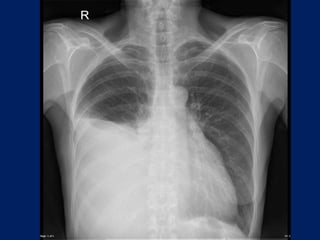

Chest radiographs may show the following:

• Pulmonary nodule, mass, or infiltrate

• Mediastinal widening

• Atelectasis

• Hilar enlargement

• Pleural effusion

Lung Cancer:

Findings on Chest X-ray

• Nodule (< 3cm) vs. Mass (>= 3cm).

– Location:

• Peripheral (Adenocarcinoma) vs.

• Central (Squamous).

– Single or multiple (metastases).

• Endobronchial obstruction.

– Atelectasis of lobe or lung.

– Pneumonia.